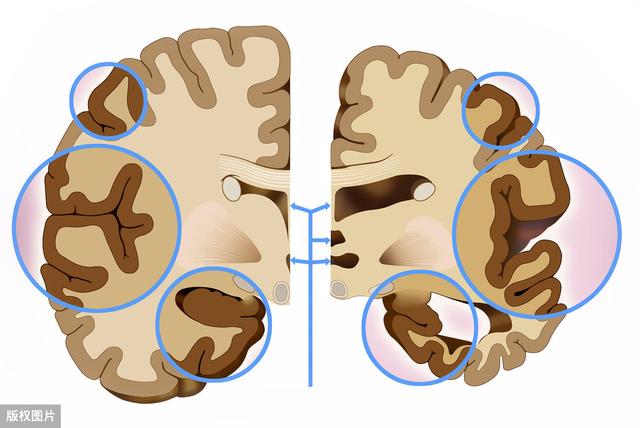

形態学的には、大脳皮質萎縮、小脳萎縮、大脳皮質、小脳および脳幹の萎縮を含むびまん性脳萎縮として現れる。限局性脳萎縮は、外傷、血管疾患、頭蓋内限局性感染症などの限定的な脳の器質的病変の後に最もよくみられる。脳萎縮の最も一般的な原因は、長期にわたる慢性的な脳血液供給不足によるもので、脳細胞が早期に死滅する。

脳萎縮は様々なタイプに分類されるが、原因や症例によって大きく5つのタイプに分類される。

小脳萎縮:小脳の病理学的変化が優勢で、臨床的には不安定な歩行、運動失調、不明瞭な言語、窒息が特徴である;

大脳萎縮:大脳皮質の萎縮を主な病理学的変化とし、主に運動機能障害、記憶障害、遅発性反射を示す;

遺伝性脳萎縮症:脳萎縮症は遺伝的要因に影響される可能性があり、診断を確定するためには遺伝子検査が必要で、常染色体優性遺伝と劣性遺伝に分類される;

限局性大脳萎縮:病変部位とその周囲に限局性の萎縮が生じ、ある種の脳症や脳損傷の後遺症とも呼ばれる;

退行性大脳萎縮症:大脳、小脳、小脳オリーブが萎縮し、程度の差こそあれ変性する。その結果、大脳低形成、神経機能障害、痴呆を主症状とする老年性疾患が多発する。

脳萎縮の部位でいえば、大脳萎縮と小脳萎縮に簡単に分類できる。大脳は言語や思考などを司り、小脳は主に平衡感覚を司る。従って、大脳が萎縮すれば、判断力、思考力、言語表現力などにある程度の影響が出ますし、小脳が萎縮すれば、主に運動失調、バランス能力の低下、歩行が不安定になります。大脳萎縮であれ、小脳萎縮であれ、患者に大きな弊害をもたらし、重度の大脳萎縮は認知症にまで発展する可能性がある。